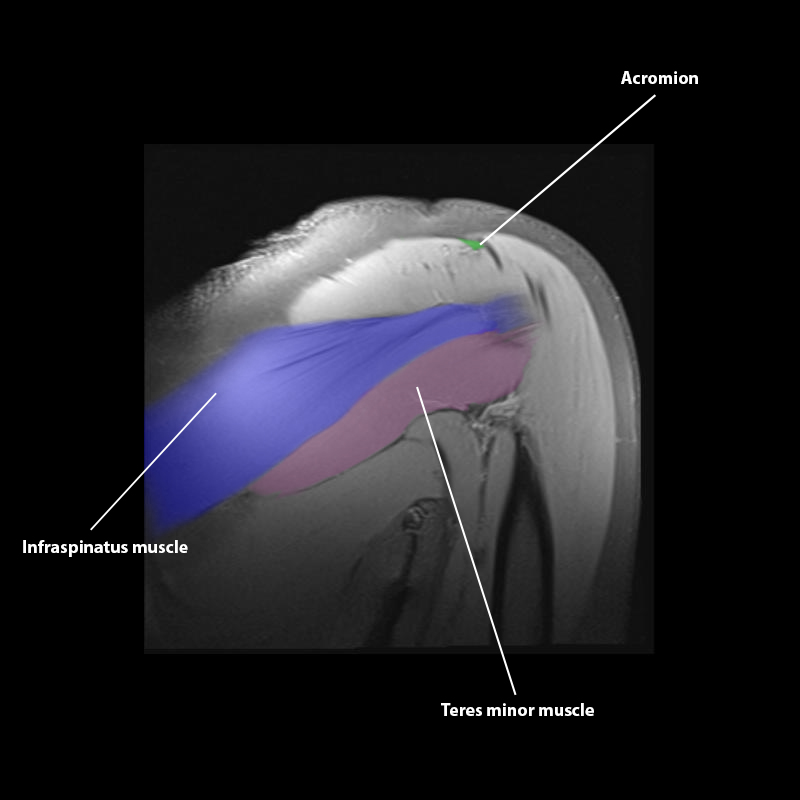

Shoulder MRI Anatomy